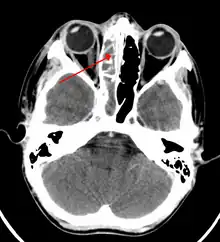

A CT scan showing sinusitis of the ethmoid sinus

For sinusitis lasting more than 12 weeks, a CT scan is recommended.[54] On a CT scan, acute sinus secretions have a radiodensity of 10 to 25 Hounsfield units (HU), but in a more chronic state they become more viscous, with a radiodensity of 30 to 60 HU.[56]